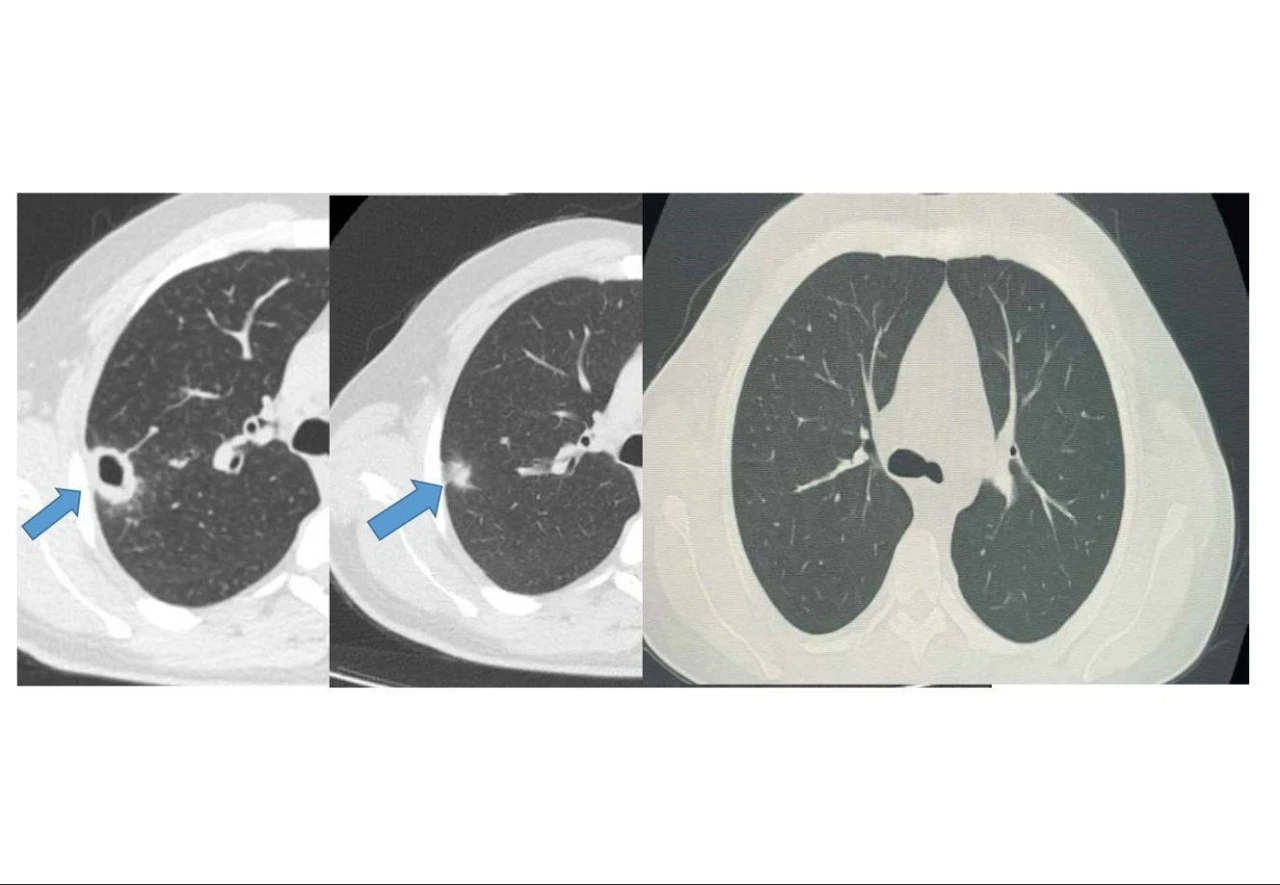

Bayburt Devlet Hastanesine öksürük ve balgam şikayetiyle başvuran 50 yaşındaki hastanın akciğerinde kitle benzeri bir doku tespit edildi. Yapılan tetkikler sonucu ciddi bir hastalık olmadığı belirlenen hasta, erken tanı ve doğru tedavi sayesinde sağlığına kavuştu.

İki haftalık tedavi sürecinin sonunda yapılan kontrollerde lezyonun neredeyse tamamen gerilediği görüldü. Sağlığına kavuşan hastanın taburcu edildiği ve durumunun iyi olduğu öğrenildi.